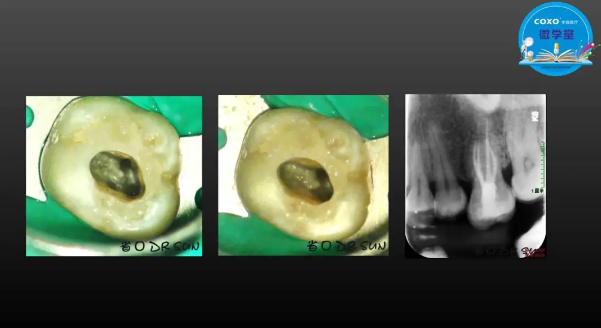

主講:孫書昱

主任醫(yī)師,牙體牙髓副主任, 廣東省口腔醫(yī)院牙體牙髓科 主任醫(yī)師。2003年碩士研究生畢業(yè),研究方向?yàn)檠荔w牙髓病學(xué),擅長(zhǎng)于牙體牙髓病的診斷、齲齒、牙髓炎、根尖周病的治療以及前牙美容修復(fù)。